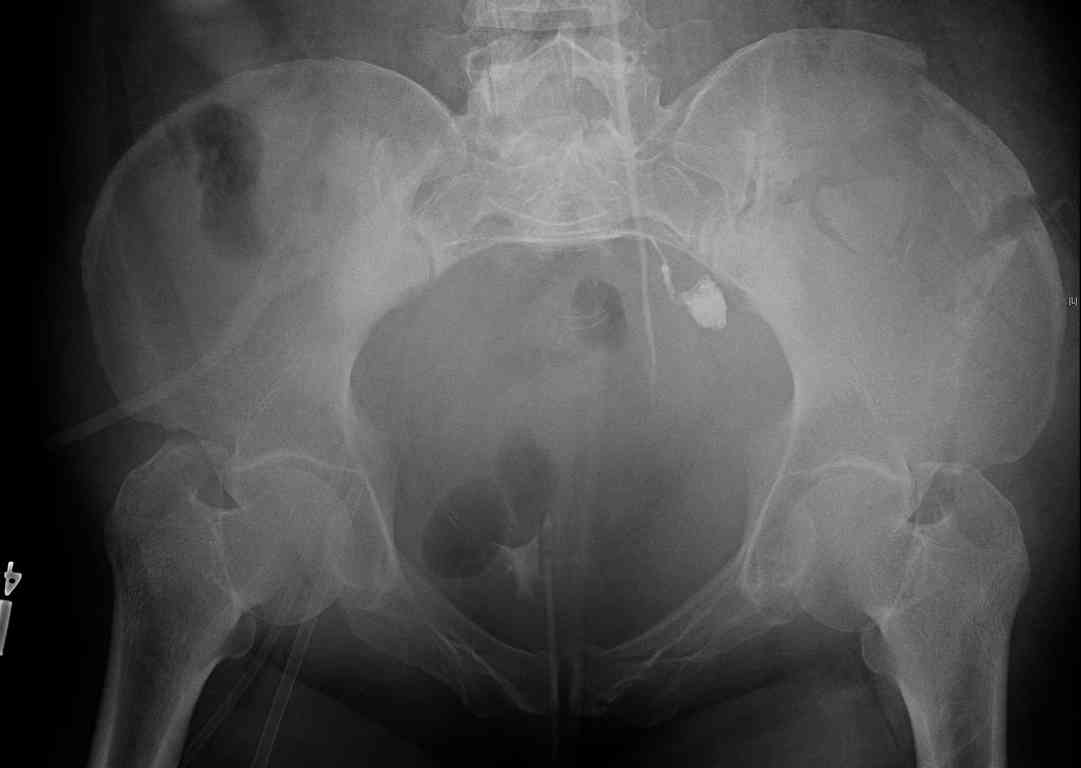

comminuted crescent fx

40 ish female ejected from car. Unstable, DPL negative, went to angio and had her pelvic bleeds embolized after many units of blood. GCS 6, floating elbow, clavicle, bothbones, etc.

My standard approach to this pelvis would be posterior, reduce/lag/plate thecrest, reduce/plate the caudal extent on the posterior crest and 1-2 lags back to front. In this case, the crest comminution seems to make plating all the way to the ASIS useless, as the plate would be on free floating fragments. Would plating the posterior extent of the fracture to secure the reduction at the SI joint and 2 screws back to front be sufficient fixation? Would anyone do a perc reduction and perc back to front screws, and would that be sufficient if the SI joint could be reduced (although I don't see how this could be accurately reduced closed). Would an ilioninguinal with a pelvic brim plate and posterior column screws be a better approach, although reducing the SI would be more indirect and less accurate?

It's a comminuted iliac fracture involving the GS notch and all that

implies...use the lateral interval of an ilioinguinal, sequentially reduce,

and fix...if you want to, you can attach the dominant unstable fragment to

both the stable posterior iliac fragment and also to the anterolateral portion of the sacrum using plates...if you choose to anchor to both, the implants get congested on the iliac side of the SI joint so be precise with contouring and such applications...perhaps and based on the images shown, an iliosacral screw would only augment the construct if applied to the second sacral segment (but this is difficult to assess on the images shown). The crest components can be held securely with screws and/or peripheral plating.

Thanks. I probably didn't include enough images on the CT, but it didn't look to me like an SI screw would be of value except into S2, which I am not

comfortable placing. I will post finals if the neurosurgeons let me operate on her. ICPs still a problem.

I always manage these percutaneously. The basic idea is to peg the AIIS fragment to the crescent frag still attached to the sacrum.

But the reported results of open treatment are very good, so your plan of ORIF should yield acceptable results.